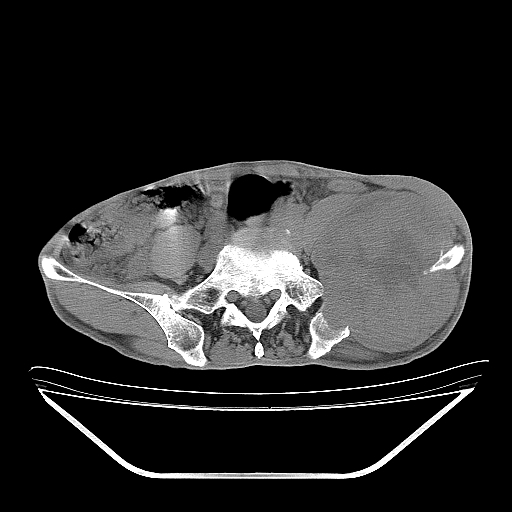

以下是引用天南地北在2007-10-4 18:01:00的发言:[br][br]考虑左髂部恶性肿瘤(溶骨性骨质破坏+软组织肿块影+残留骨质);以滑膜肉瘤可能性大。[br]建议穿刺活检

以下是引用liuyue在2007-10-4 23:38:00的发言:[br]左髂部恶性肿瘤,建议穿刺活检,或先做肺部检查,除外肺癌转移之可能。